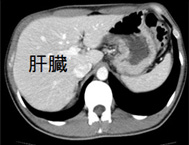

正常な肝臓